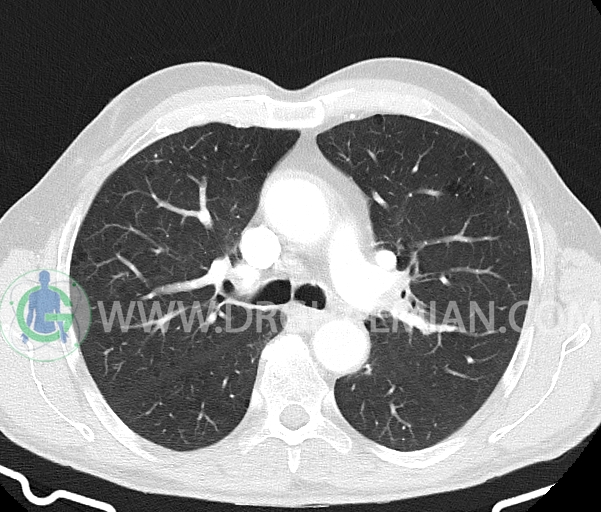

در سی تی اسکن اسپیرال ریه و مدیاستن- شکم و لگن با و بدون کنتراست خوراکی و وریدی (مولتی دیدکتور 16 با مقاطع ظریف و بازسازی های ساژیتال و کرونال) :

– آمفیزم سنتری لوبولار در لوب فوقانی هر دو سمت با ارجحیت در سمت راست

–آمفیزم پاراسپتال در هر دو ریه

–ندول Solid با حدود صاف به سایز 6x5mm (متوسط 6mm) در سگمان پوستریور بازال لوب تحتانی راست (تطبیق با مدارک قبلی )

– ندول پری فیشرال به سایز 6mm در فیشر مینور راست (بدون اهمیت بالینی )

–چند لنف نود در مدیاستن میانی و قدامی به حداکثر SAD=8mm در پره کارینا (بدون اهمیت بالینی)

–دو لنف نود در هیلوم ریه راست به حداکثر SAD=8mm